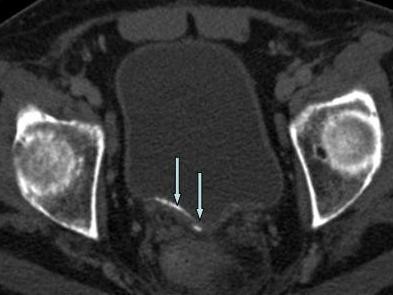

An unusual case of chronic urinary retention and bladder ...

An unusual case of chronic urinary retention and bladder ... from casereports.bmj.com